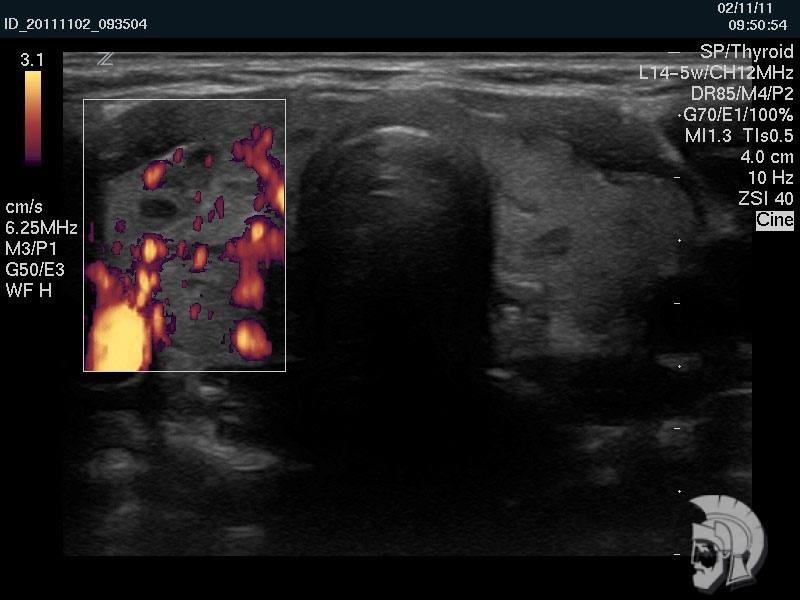

Фото щитовидной железы. Тот же случай. При исследовании в режиме энергетического допплера в правой доле щитовидной железы определяется выраженное усиление кровотока |

Обратите внимание на совершенное качество фотографий, свидетельствующих об экспертном классе аппаратов УЗИ!

Использование ультразвуковых аппаратов экспертного класса с режимами энергетического допплера и цветового допплера позволяет врачам Курортной клиники мужского здоровья выявить патологические изменения щитовидной железы на ранних этапах.